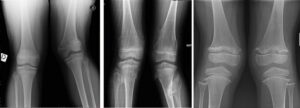

E’ fondamentale in preparazione ad un’eventuale chirurgia, eseguire una radiografia in maniera corretta. Questo consente di calcolare gli assi meccanici e quantificare a pieno la deformità. Non è infrequente infatti una discrepanza tra esame clinico e esame radiografico: può capitare che pazienti che mostrano un valgismo significativo clinicamente, abbiano poi in realtà una deviazione dell’asse modesta, che non necessita di un intervento chirurgico.

Per essere eseguita correttamente ed evitare errori di misurazione, la radiografia degli arti inferiori effettuata in piedi. Devono essere visualizzati femore e tibia sulla stessa immagine in modo da poter effettuare il calcolo degli assi, devono essere visualizzati il bacino e l’ala iliaca per verificarne i nuclei di crescita (Risser e cartilagine triradiata).